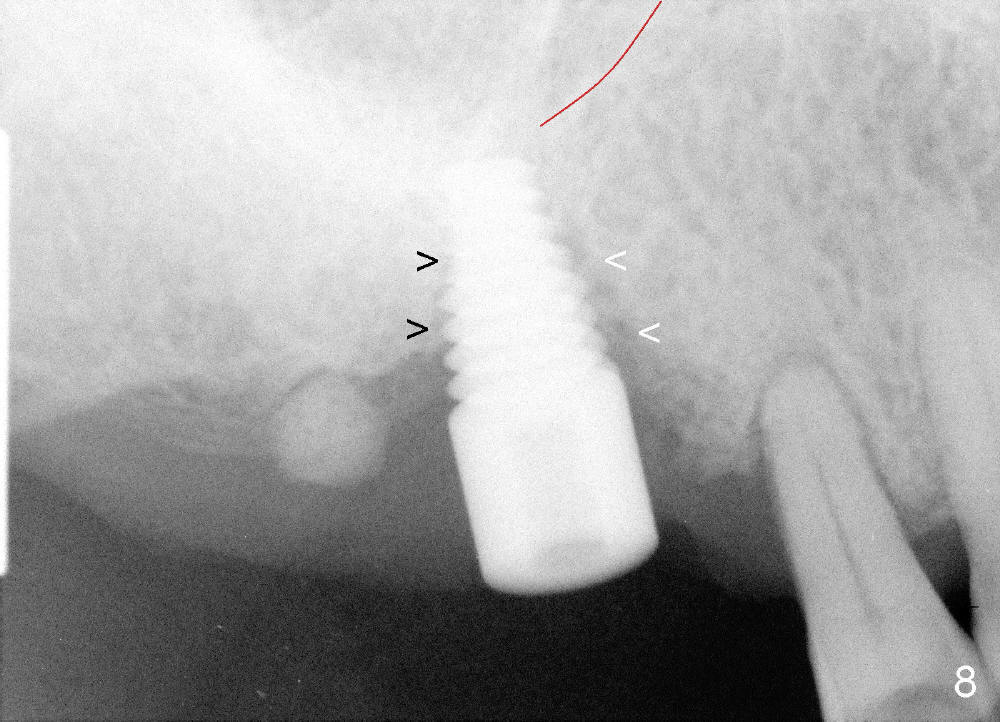

Osteotomy can be done in the palatal socket or the septum in this case to avoid implant thread exposure. Initial osteotomy is created in the palatal socket by using series of tap drills (4.5,5,6,7x17 mm) without stability or enough length (Fig.5; red line: sinus floor). The second osteotomy is made in the septum by using series of tapered osteotomes (2,3,4x17 mm), followed by 4.5x20 mm tap at depth of 17 mm with satisfactory binding (Fig.6). To avoid further sinus penetration and close the socket as much as possible, 5 and 6x17 mm taps are used at 14 mm deep (Fig.7). Nasal blowing reveals air leaking after the last tap. A 6x14 mm tapered implant is placed with insertion torque >60 Ncm (Fig.8). No bone graft is placed. The implant is surrounded by gingiva proximally and lingually and coagulation buccally. The wound is covered by perio dressing.

There is no nasal hemorrhage intra or postop. The implant is covered buccally by healing gingiva 7 days postop (Fig.9). It appears that the gingiva has strong regenerative potential. The buccal gingiva looks normal 3 months postop (Fig.10 healing cuff is placed over the implant). The implant appears to have osteointegrated (Fig.11).